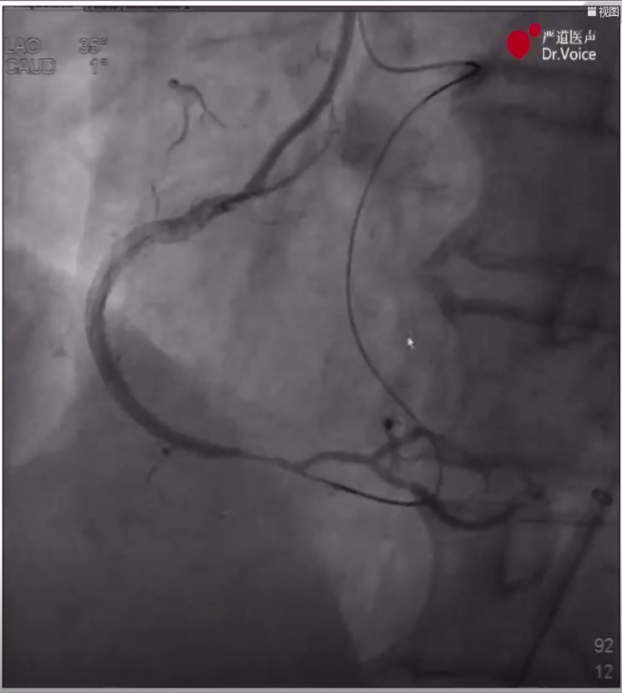

3、经右股动脉8F抗折鞘送入7F XB3.5指引导管至左冠,造影及IVUS提示LAD开口严重狭窄并钙化,在IVUS指导下完成LM-LAD支架植入,造影显示效果满意。

LAD近端血管病变

LAD近端支架植入后效果